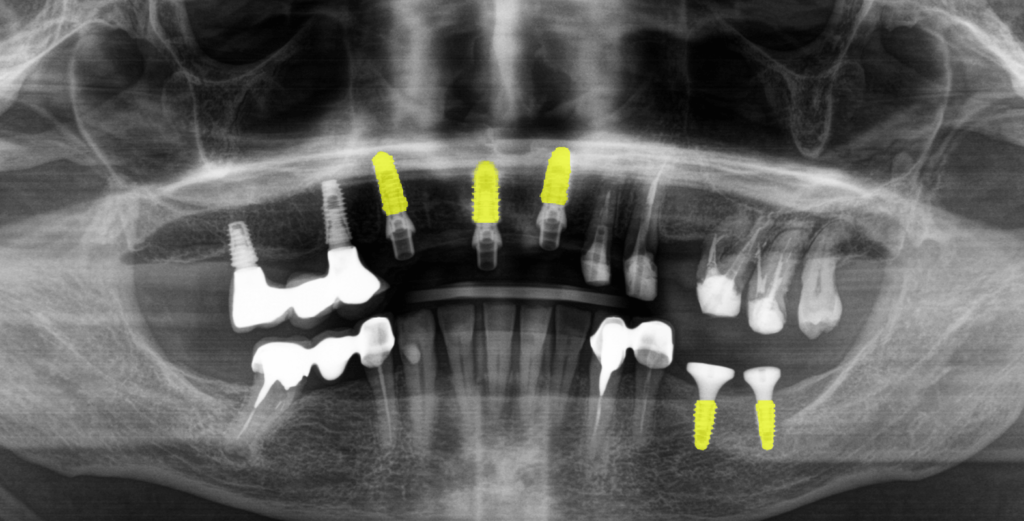

После анализа данных полученных путем компьютерной томографии и при очном осмотре было обнаружено:

- Установленный мостовидный протез на зубах 4.4 и 4.6 (зуб 4.5 отсутствует).

- Зубные коронки на зубах 3.3 и 3.4

- Зубы 3.6 и 3.7 отсутствуют.

- Имплантаты в области недостающих зубов 1.4, 1.6 и металлокерамический мостовидный протез на них с винтовой фиксацией.

- На зубах 1.3, 1.2, 2.1, 2.2, 2.3, 2.6 и 2.7 (2.4 и 2.5 отсутствуют) установлен металлокерамический мостовидный протез на родных зубах, который был подвижен и снимался вместе с вкладками.

- Зубы 1.2, 1.3 и 2.1 расколоты.

- Зуб 1.5 отсутствует.

- Кариозное поражение зуба 2.8

- Зубы 1.6 и 1.7 депульпированы.

- Катаральный гингивит на слизистой верхней челюсти (как следствие регулярного раздражения от подвижного металлокерамического протеза).